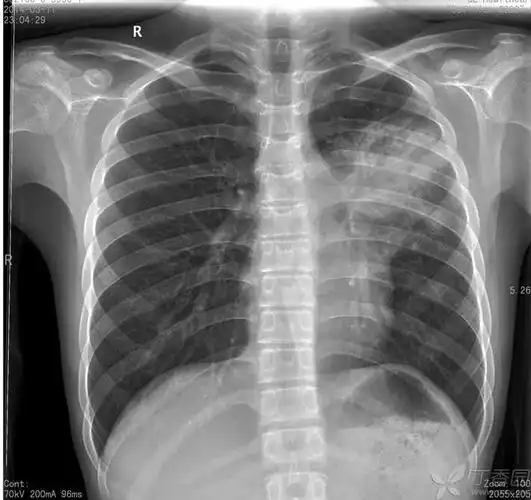

病例分享儿童大叶性肺炎为什么气管镜冲洗

于2014-02-27拍胸片,诊断为大叶性肺炎; 在当地诊所抗炎治疗,10天左右